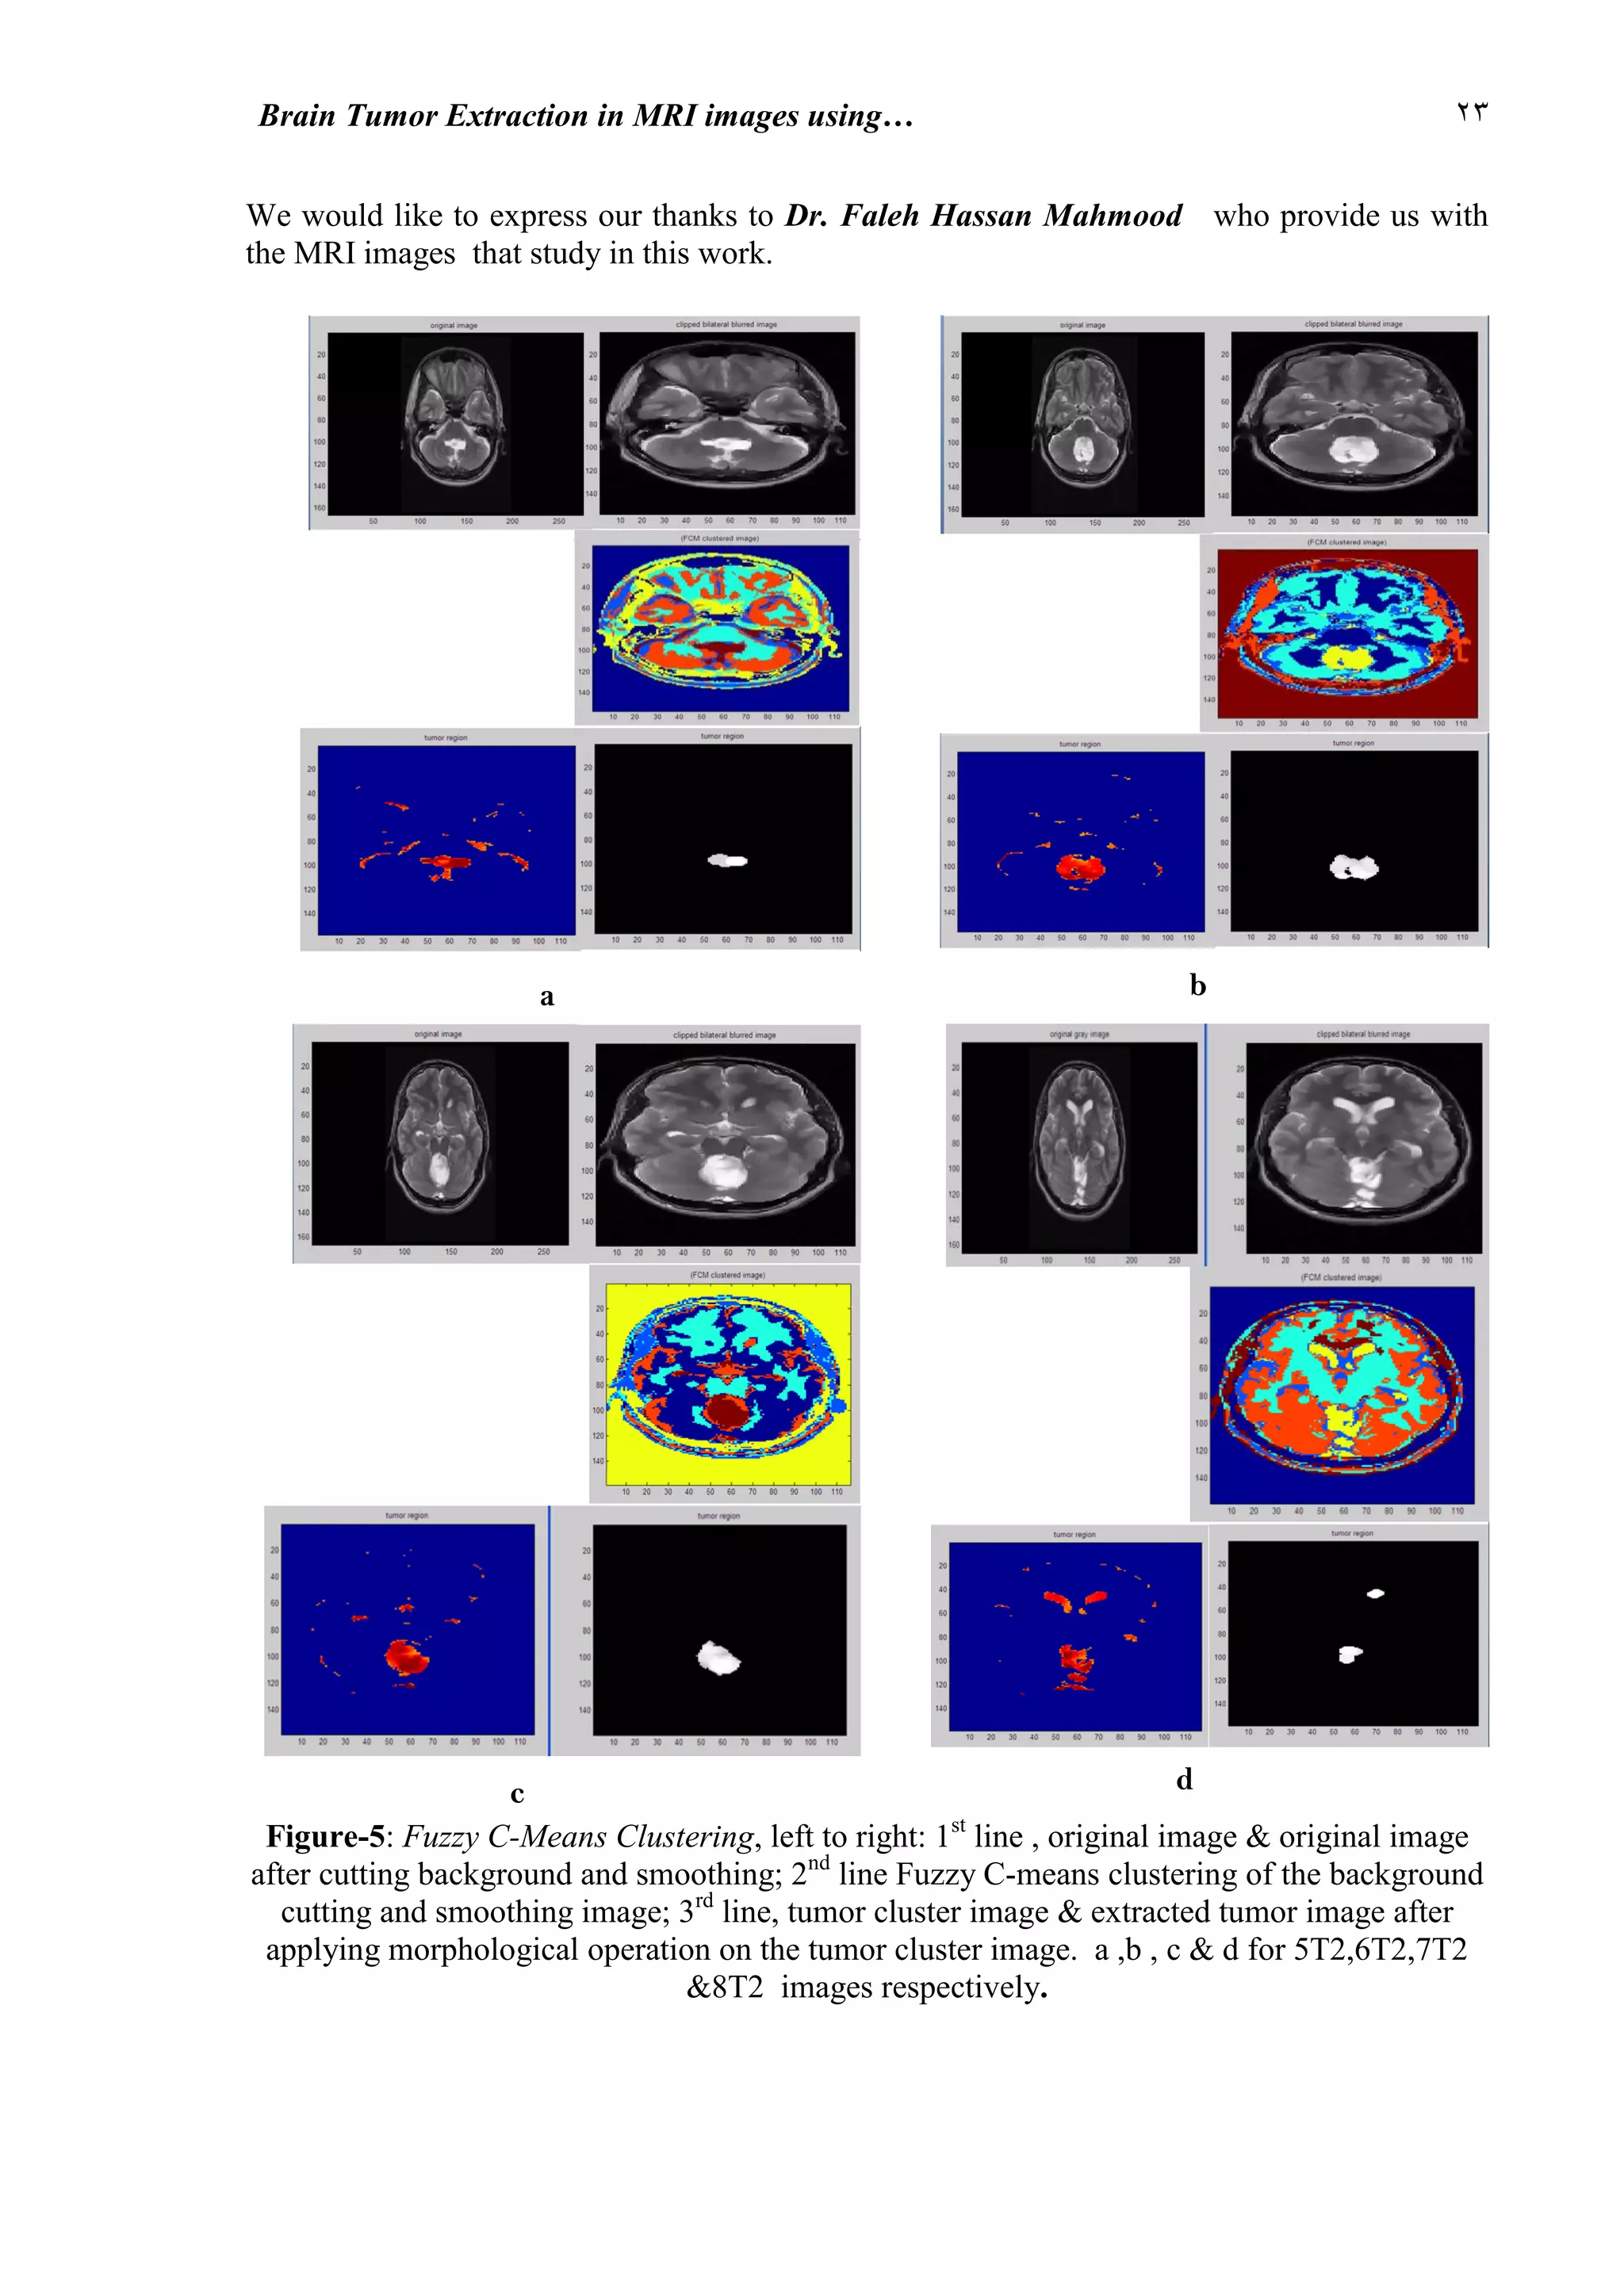

Figure-5: Fuzzy C-Means Clustering, left to right: 1st

line , original image & original image

after cutting background and smoothing; 2nd

line Fuzzy C-means clustering of the background

cutting and smoothing image; 3rd

line, tumor cluster image & extracted tumor image after

applying morphological operation on the tumor cluster image. a ,b , c & d for 5T2,6T2,7T2

&8T2 images respectively.

s technique is implemented on the input MRIs (with cluster number equals to 6 ) . The

segmented image including the cluster of the tumor was selected and opening morphological

operation with structure element of shape disk (four pixels diameter) for images 5T2, 6T2,

7T2 & 8T2. The resulted image is then convoluted with the original image to acquire the

image of the tumor region, shown in fig-5. The tumor region's surface area is listed in Table-1.